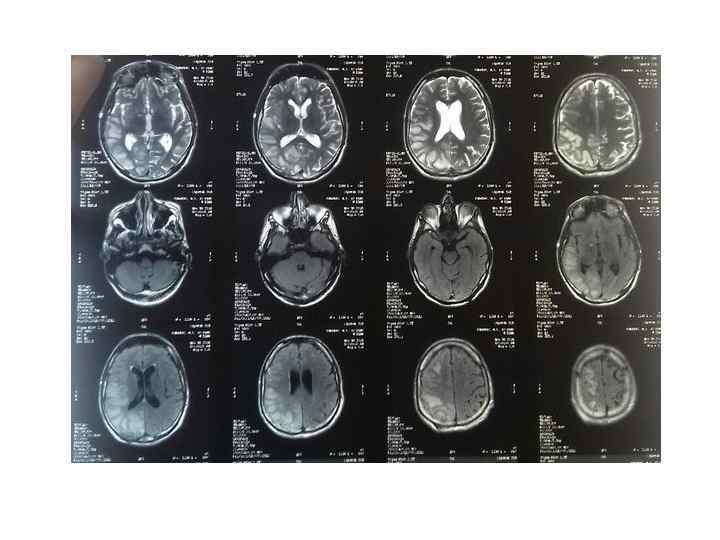

МРТ как более эффективный метод РКТ Т 2 FLAIR Т 2 -ВИ DWI

Острая стадия тромбоза (1– 4 сутки) Т 1 -ВИ: тромб изоинтенсивен Т 2 -ВИ: тромб гипоинтенсивен

Подострая стадия (тромб гиперинтенсивен) Т 2 -ВИ (10 -15 день) Т 1 -ВИ (5 -9 день) Т 2 FLAIR (5 -9 день)

Венозный инфаркт на МРТ • Зона измененного МР-сигнала с локализацией, нехарактерной для какоголибо артериального бассейна • Вазогенный отек зоны, которую дренируют пораженный синус , часто сопровождается очагами кровоизлияний • Цитотоксический отек в зоне вторичного венозного инфаркта. • На ИКД-карте возможно сочетание пониженного и повышенного ИКД